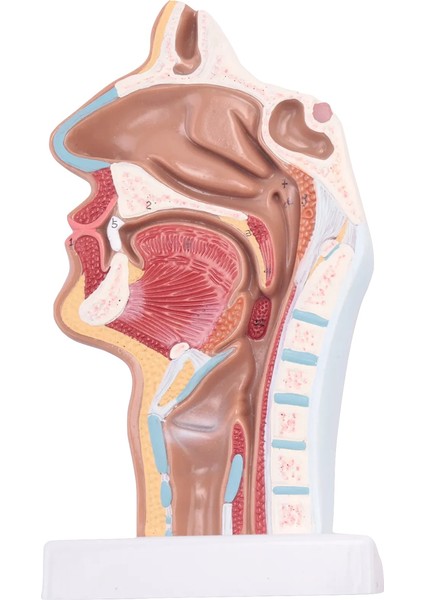

Qcuiil Fen Bilimleri Sınıfı Çalışma Gösterimi Öğretim Modeli Için Insan Anatomik Burun Boşluğu Boğaz Anatomisi Modeli (Yurt Dışından)

Fen Bilimleri Sınıfı Çalışma Gösterimi Öğretim Modeli Için Insan Anatomik Burun Boşluğu Boğaz Anatomisi Modeli (Yurt Dışından)

Türkçe: 1. Bu model ağız, burun, yutak ve gırtlağın iç yapısını ve serebrovasküler ve kranial sinirler gibi yapıları gösterir. (dijital işaretli) 2. Bu olağanüstü anatomik model insan burun boşluğu boğazının harika bir görünümünü sunar. 3. Hasta eğitimi veya anatomik çalışmada kullanılmak üzere bir tabana monte edilmiş insan gerçek boyutlu burun boşluğu boğaz modeli. 4. Anatomik modeller genellikle bilimsel sınıflarda ve ofis ortamlarında eğitim aracı olarak kullanılır. 5. Yüksek kaliteli PVC'den yapılmıştır. Anatomi araştırmalarına derinlemesine ve uygun maliyetli bir yaklaşım sağlar. Boyut: 24*12*12cm Renk: kırmızı + sarı Malzeme: PVC Paket İçeriği: 1 * İnsan burun anatomik modeli Yalnızca yukarıdaki paket içeriği, diğer ürünler dahil değildir. Not: Hafif çekim ve farklı ekranlar, resimdeki öğenin renginin gerçek olandan biraz farklı olmasına neden olabilir. İzin verilen ölçüm hatası +/- 1-3 cm'dir.Ürün özellikleri